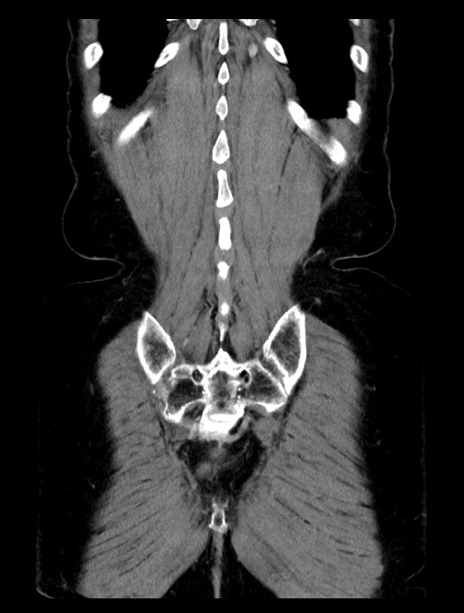

横断像

症例23(冠状断像)

【症例】70歳代女性

【主訴】下腹部痛・嘔吐

【現病歴】2日前より腹痛あり。昨日嘔吐あり。症状改善しないため来院。

【既往歴】胃GISTに対して胃部分切除後。

【身体所見】BT 37.1℃、BP 128/77mmHg、腹部:平坦・軟、下腹部に圧痛あり。

【データ】WBC 10200、CRP 0.31